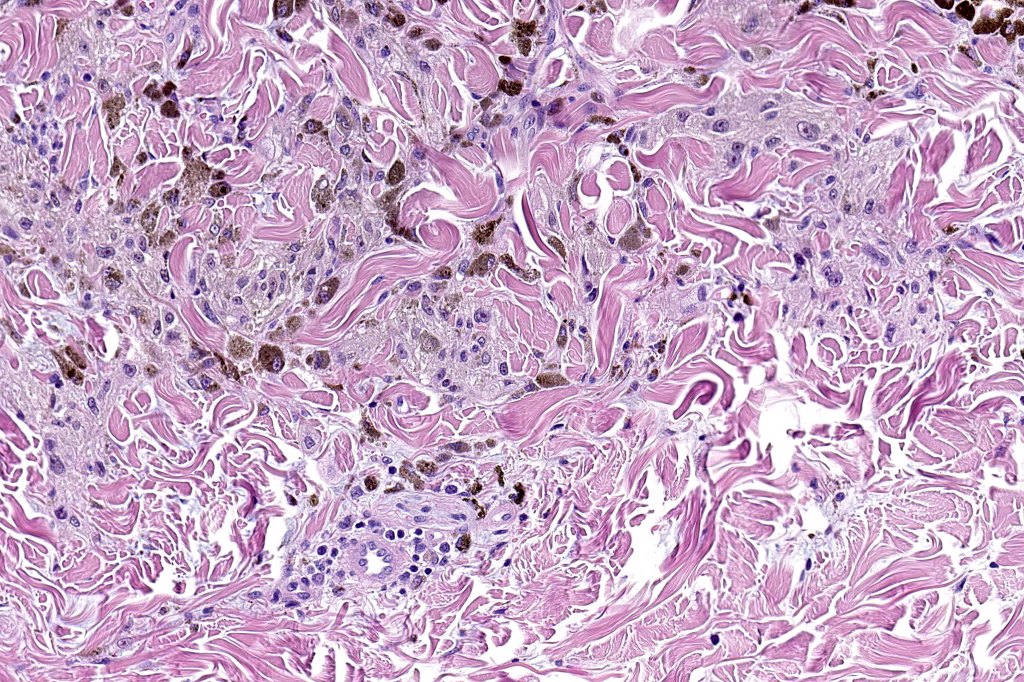

•Symmetrical, circumscribed wedge-shaped infiltrate-most common growth pattern with the broad base uppermost, deeper aspect extends along appendageal structures & neurovascular bundles with a fasciular or plexiform pattern

•Deep spindle cells

•Melanophages

. Perineural spread sometimes seen, infiltration of arrector pili muscles common